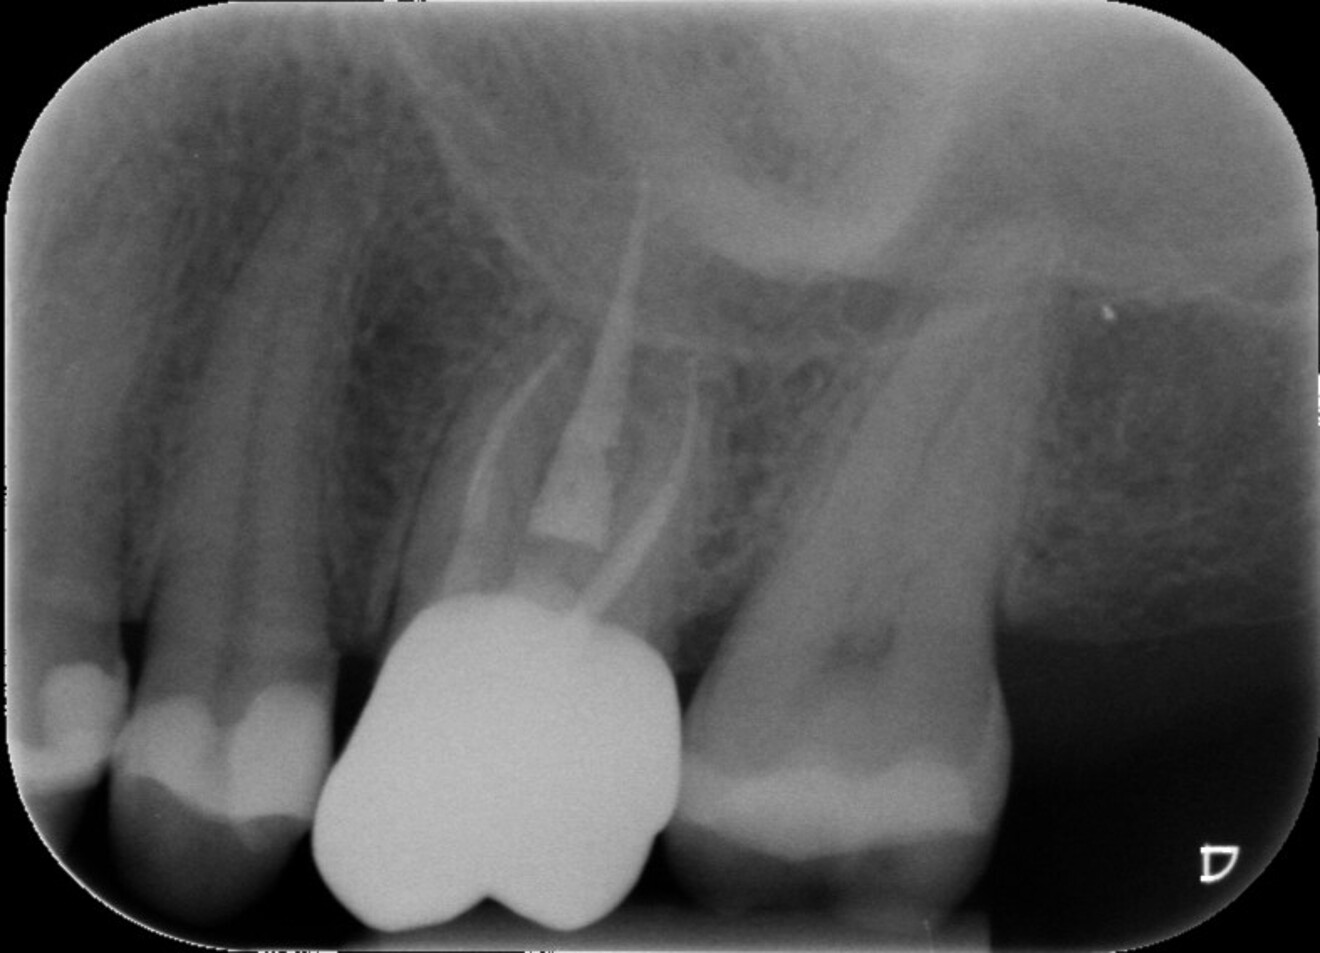

Fig. 1 : Radiographie préopératoire montrant la présence d’une reconstitution corono-radiculaire coulée, ancrée dans les trois canaux.

D’un point de vue pratique, la première étape consiste à réduire les dimensions du tenon s’il occupe une grande partie de la structure coronaire, de préférence en lui donnant une forme cylindrique similaire à celle d’un tenon préfabriqué. De même, une reconstitution corono-radiculaire coulée ancrée dans plusieurs canaux doit d’abord être sectionnée jusqu’au niveau du plancher de la cavité pulpaire, afin de la traiter comme un ensemble de tenons unitaires, ce qui diminue le degré de rétention global du système. La réduction du tenon doit être effectuée avec des fraises en carbure spécialement conçues pour découper le métal, sous une irrigation abondante. Les évaluations cliniques et radiographies préliminaires sont essentielles pour planifier l’angle de coupe. La procédure doit être fréquemment vérifiée et, si nécessaire, il convient d’effectuer des contrôles radiographiques avant qu’une quantité excessive de dentine ne soit sacrifiée (Figs. 1–3).